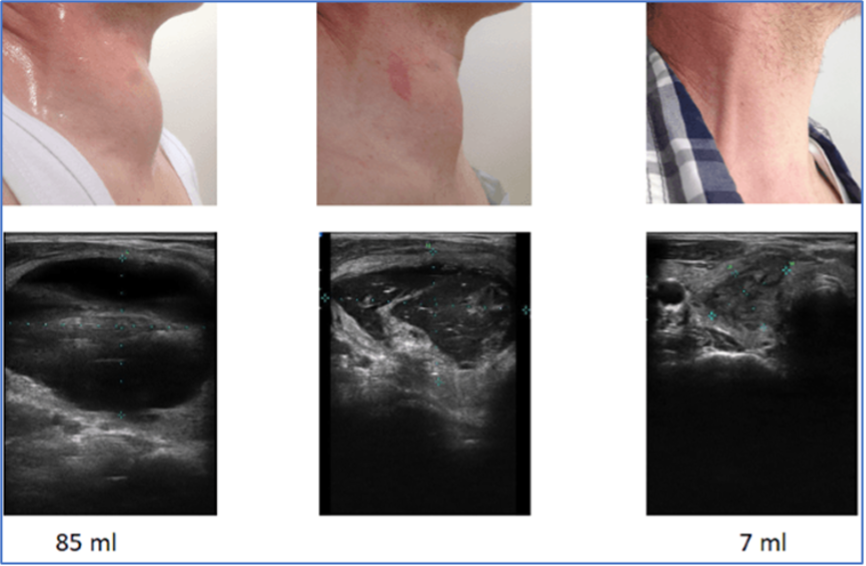

Киста щитовидной железы: объем узла более 85 мл (куб. см), а через 3 месяца — 7 мл (куб. см).